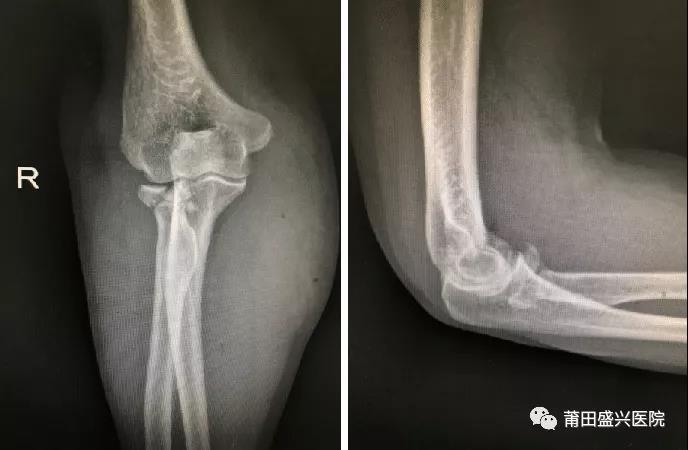

對(duì)于成人橈骨頭骨折Mason III型來說,橈骨頭就成為維持肘關(guān)節(jié)軸向和外翻穩(wěn)定的主要……